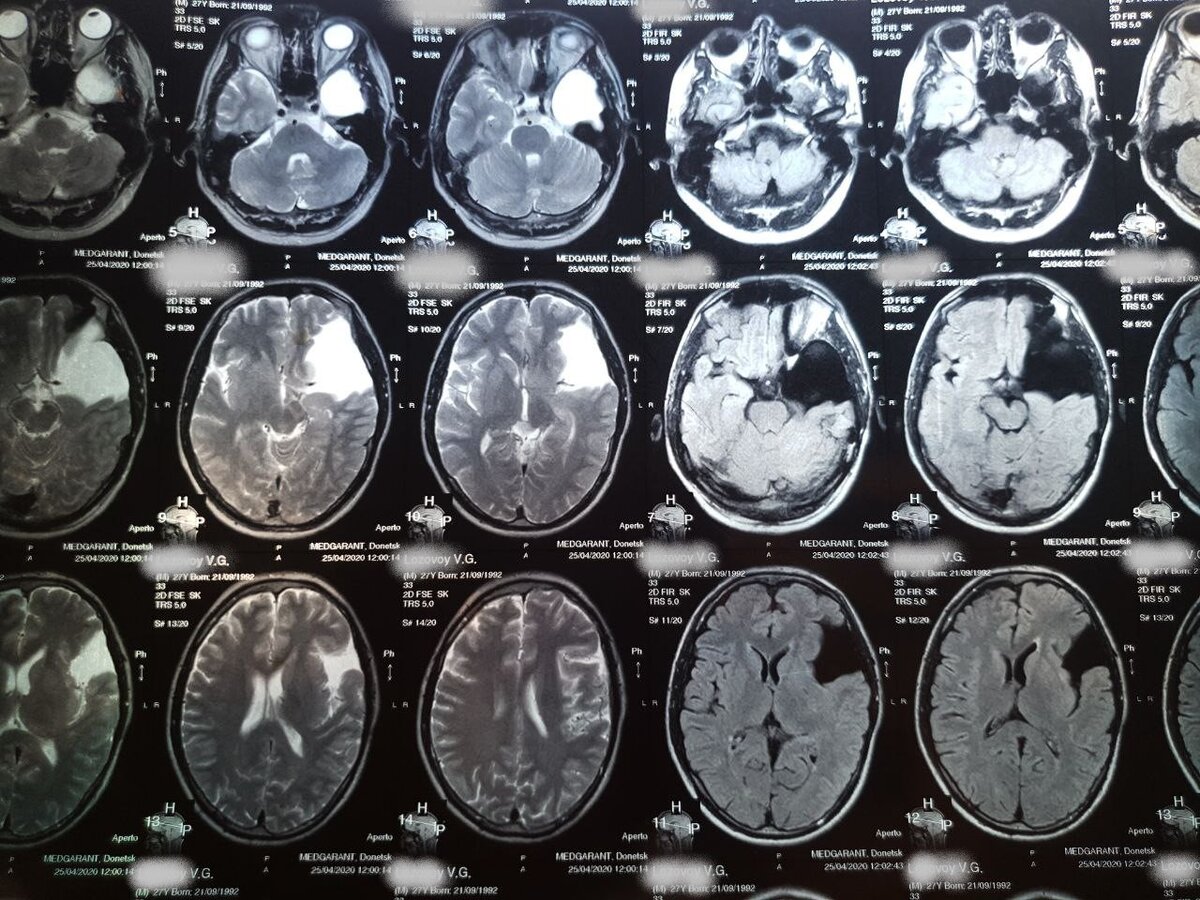

Мой снимок МРТ, наблюдаюсь с 2012 года. Арахноидальная киста размерами 6х6х5,5 сантиметров.